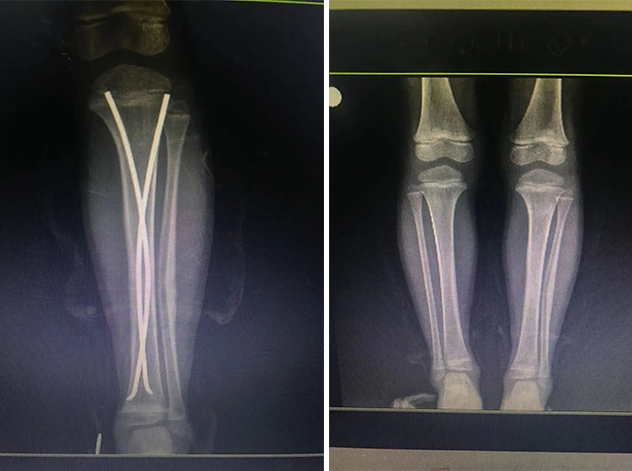

在接下來(lái)的康復(fù)過(guò)程中,睿睿非常配合,恢復(fù)的非常好。今年4月12日,睿睿拆除了左腿里的彈性釘。

拆前拆后對(duì)比